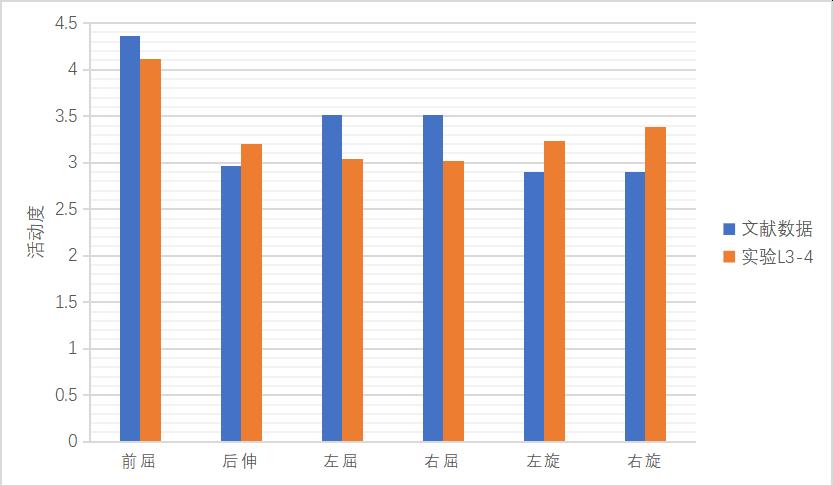

对L5椎体的下表面进行约束固定���,在 L3椎体上表面施加大小为500 N垂直向下的压力负荷��,充分反映健康人垂直站立时的腰椎承重情况��,同时在该表面节点及横突及棘突上表面施加 10 Nm的扭力负荷��,并加载前屈���、后伸���、左侧屈����、右侧屈����、轴向左旋转及轴向右旋转6种状态�����,其他约束条件不变��,可获得脊柱在6种功能状态下腰椎活动度的数值����,测量各节段的腰椎活动度�����,见图 14�����、图 15����。

图 14 L3-4模型有效性验证

1����、正常有限元模型(M0)L3-4节段在前屈���、后伸�����、左屈����、右屈����、左旋���、右旋的活动度为4.12°����、3.2°����、3.04°����、3.02°����、3.23°�����、3.38°��;L4-5节段在前屈�����、后伸���、左屈����、右屈��、左旋����、右旋的活动度为4.46°���、3.42°��、3.36°�����、3.76°��,4.35°���,4.26°��。与文献比较���,模型中各节段不同状态活动度数据均在正常范围之内���,证明该模型基本符合人体实验����,可用于有限元相关研究��。